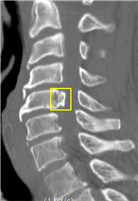

- 데이터 종류 예시

대표도면 데이터 종류 예시 데이터 종류 경추x-ray 흉추 MRI 흉추CT 예시

데이터 구성 경추 디스크의 높이

경추 각 추체에 대한 bounding boxT2 axial image에서 흉추5-6번 구간의 면적

T2 axial image에서 척수 영역에 대한 외곽선흉추골화증평가

흉추골화증 병변에 대한 bounding box데이터 포맷 원본: dicom,

학습데이터: jpg

어노테이션: txt

ROI: JSON원본: dicom

대표도면 질환별 라벨링 예시 구분 X-ray MRI CT 퇴행성 경추협착증 (DCS)

데이터 포맷 dicom 포맷, json 포맷 dicom 포맷, json 포맷 dicom 포맷, json 포맷 대표도면 질환별 라벨링 예시 구분 MRI CT 흉추 척수증 (DTM)